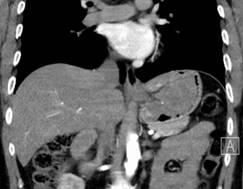

患者杨XX,男,42岁、BMI25.5,因“解黑便伴头昏、乏力1+月”于普外一科住院。伴有心慌、乏力、气促,面色、甲床、睑膜苍白。检查提示胃底贲门巨大肿瘤伴出血,重度贫血。患者胃肿瘤约拳头大小,位于胃底贲门处,距贲门较近。术前全科讨论、患者肿瘤大、距离贲门近,无法行肿瘤楔形切除,拟定行近端切除、残胃保留、双通道吻合。

腹腔镜术中探查证实肿瘤位于贲门口,肿瘤巨大,无法行楔形切除,遂行开腹近端胃切除、残胃保留、双通道吻合。手术顺利,术后患者恢复佳。目前患者以近流食、进食后无腹痛、腹胀、恶心、呕吐、吞咽困难,无返酸、嗳气、烧心、胸骨后烧灼样刺痛等不适。

术后病检回示胃底贲门巨大胃间质细胞瘤、中度侵袭危险性。